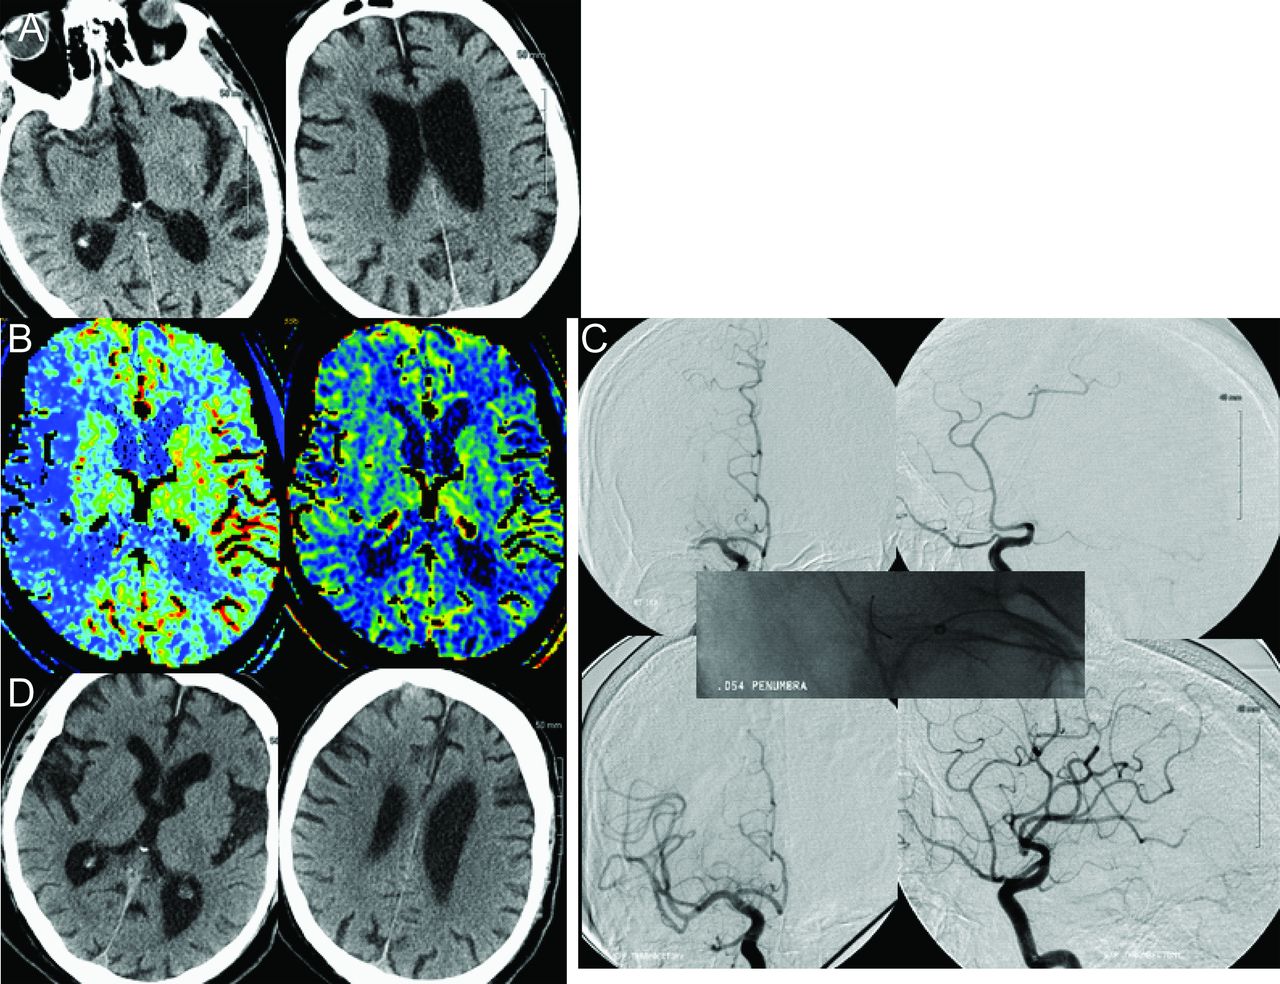

一个74岁的老人(图2)和心房纤维性颤动的历史发展左突然发作的弱点。他与左半身不遂,急诊面部的弱点,和严重的构音障碍署12分)从症状出现在4.5小时。最初的头部CT显示高密度MCA的迹象。头部的CT血管造影显示右大脑中动脉近端闭塞与CT灌注明显不匹配。使用054 PS后45分钟的愿望,初始阻塞改善与后续几乎完全从TIMI 0 TIMI 3神经在24小时内恢复。病人出院回家独立生活的夫人得分1。